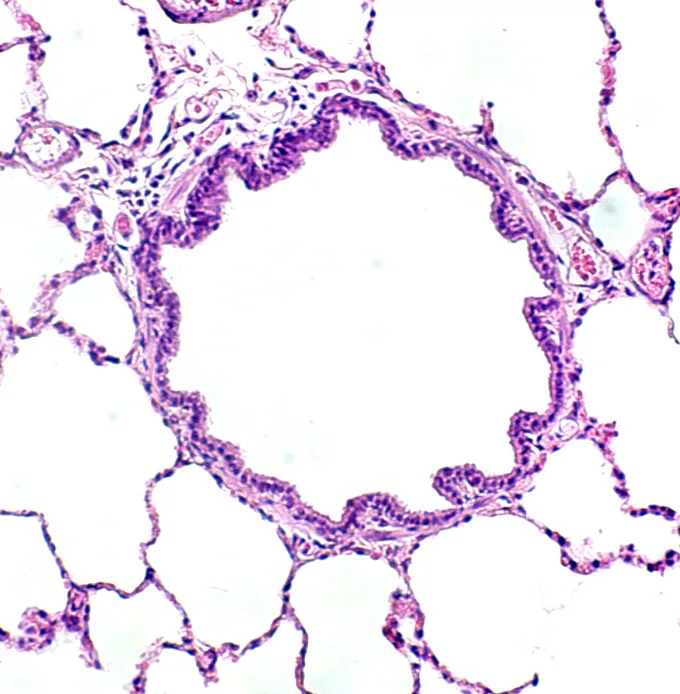

It is essential to maintain patency of all the ductwork (ie, air passageways from the nares to the smallest bronchiolar ducts) (Figure 2A).

FIGURE 2 A patent airway in a healthy cat (A). An occluded airway from a cat with chronic disease (B). Intraluminal mucus and debris, smooth muscle thickening, numerous inflammatory cells and goblet cells, and subbasement membrane thickening are evident.

Normal ventilation requires a patent ductwork and functioning air pump. Any clogging, bending, or excessive narrowing of ductwork will substantially reduce airflow into (and out of) the lungs, leading to an obstructive type of breathing pattern.